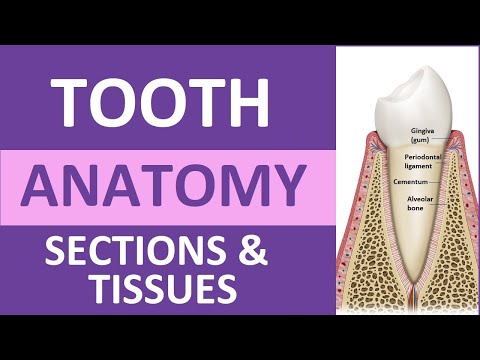

Tooth Anatomy: Structure & Tissues | Crown, Neck, Root, Dentin, Cementum, Enamel, Pulp

Tooth

The Anatomy and Function of Dental Roots